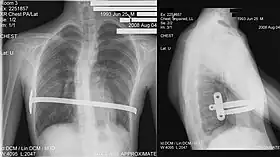

Pectus excavatum requires no corrective procedures in mild cases.[22] Treatment of severe cases can involve either invasive or non-invasive techniques or a combination of both. Before an operation proceeds several tests are usually performed. These include, but are not limited to, a CT scan, pulmonary function tests, and cardiology exams (such as auscultation and ECGs).[23] After a CT scan is taken, the Haller index is measured. The patient's Haller is calculated by obtaining the ratio of the transverse diameter (the horizontal distance of the inside of the ribcage) and the anteroposterior diameter (the shortest distance between the vertebrae and sternum).[24] A Haller Index of greater than 3.25 is generally considered severe, while normal chest has an index of 2.5.[19][25][26] The cardiopulmonary tests are used to determine the lung capacity and to check for heart murmurs.[27]

His two-stage procedure, widely known as the Nuss procedure, involves slipping in one or more concave steel bars into the chest, underneath the sternum.[56]

The bar is flipped to a convex position so as to push outward on the sternum, correcting the deformity. The bar usually stays in the body for about two years, although many surgeons are currently moving toward leaving them in for up to five years. When the bones have solidified into place, the bar is removed through outpatient surgery.